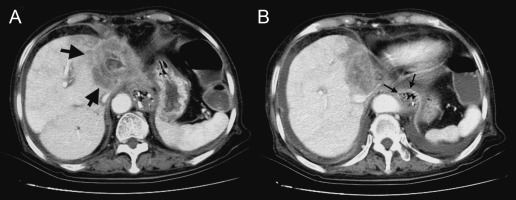

Physical examination demonstrated a thin woman. Her height was 158 cm and weight 48 kg. Her abdomen was soft without rebound tenderness. The laboratory tests were normal, apart from hypokalemia (K 3.4 mmol/L, normal range 3.5–5.3 mmol/L) and normocytic anemia (Hb 11.9 g/dL, normal range 12–14 g/dL). An esophagogram demonstrated a markedly dilated esophagus with a “bird-beak” appearance at the GE junction (Fig. 2 ). Idiopathic achalasia was preliminarily diagnosed based on the above findings, although the patients age and short duration of symptoms were not consistent with the diagnosis. Repeated EGD demonstrated a very tight GE junction (Fig. 3 A) with retention of some food residues and pills in the lower third of the esophagus (Fig. 3 B). Besides, the endoscope could not pass the GE junction into the stomach. However, esophageal manometry demonstrated a normal pattern of esophageal peristalsis. Based on the endoscopic findings and manometric features, pseudoachalasia was suspected. Abdominal computed tomography demonstrated a hypovascular tumor in the left lobe of the liver (Fig. 4 A, arrows). Moreover, the tumor encased the lower end of the esophagus (Fig. 4 B, arrows). Thus, the diagnosis of pseudoachalasia caused by liver tumor was made. At laparotomy, the liver tumor was deemed unresectable and biopsy specimens were taken. A pathological examination of the biopsy specimens showed cuboidal tumor cells with pleomorphic and hyperchromatic nuclei arranged in a ductular or glandular pattern within the desmoplastic stroma, the findings being consistent with cholangiocarcinoma (Fig. 5 ). Finally, the patient died due to disease progression 1 year later.

Abdominal computed tomography. (A) A hypodense tumor located in the left lobe of ...

Figure 4.

Abdominal computed tomography. (A) A hypodense tumor located in the left lobe of the liver (arrows). (B) The tumor encased the gastroesophageal junction of the esophagus (arrows).

It is often difficult to distinguish between pseudoachalasia and idopathic achalasia based on the clinical features, radiologic images, and endoscopic findings. Certain historical features can help raise the suspicion of the presence of a malignant tumor. A short duration of symptoms (<1 year), presentation later in life (at the age of 50–60 years), and unexplained weight loss (6.8–9.0 kg) are all more typical of malignancy than of idiopathic achalasia [8]  ;  [9] . Although a few studies have reported that these criteria are poor predictors of malignancy and are not especially helpful in individual cases, the clinical features of our patient were all compatible with the abovementioned criteria. Moreover, esophageal manometric findings of a hypertensive (48 mmHg), nonrelaxing LES and a total lack of esophageal peristalsis may be indicative of achalasia. In our present case, an esophagogram demonstrated a markedly dilated esophagus with a typical bird-beak appearance, leading to the initial diagnosis of idiopathic achalasia. However, repeated EGD showed stenosis of the GE junction, and esophageal manometry revealed a normal pattern of esophageal peristalsis, not suggestive of idiopathic achalasia. A reasonable explanation for the presentation of pseudoachalasia in our patient is that the tumor cells encircled the distal esophagus, producing a constricting segment, but did not infiltrate the esophageal myenteric plexus or directly affect the vagus nerves.